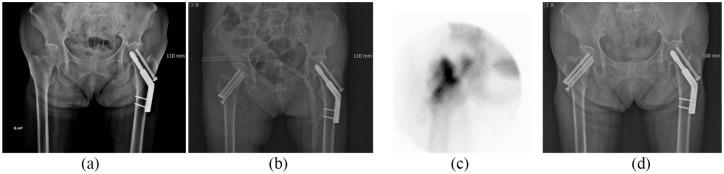

To evaluate the predicting value of Tc-hydroxydiphosphonate (HDP) pinhole bone scan in development of osteonecrosis of femoral head (ONFH) in patients with femoral neck fracture after cannulated screw fixation.

Pinhole bone scan of patients with metallically fixed femoral neck fracture from 2001 to 2015 were retrospectively reviewed. Initial pinhole bone scan was obtained within 2-3 weeks after surgery. Findings of initial pinhole bone scan were divided in to 4 groups. Group CU included cold defect in affected femoral head, group HU with no cold defect. Group PP with increased uptake along the inserted screws and group PN with no increased uptake along the inserted screws. More than 6 months of follow-up with pinhole bone scan and clinico-radiological evidence for ONFH was reviewed.

72 patients (mean age 54.01 years, male 22, female 50) were included. 19 patients were in group CU, 53 in group HU. 60 patients were in group PP, 12 in group PN. During the follow-up, 13 patients were diagnosed as ONFH. 9 (47.36%) patients in group CU developed ONFH and 4 (7.5%) in group HU. 4 (6.66%) patients in group PP developed ONFH and 9 (75%) in group PN.

To predict ONFH of femoral head followed by neck fracture, many imaging techniques with variable results were known. In this study, cold defect in early postoperative pinhole bone scans could predict ONFH, and loss of increased uptake along screw inserted site could be a strong indicative sign of ONFH. Further evaluation with a larger population is necessary.

评估 Tc-羟膦酸盐(HDP)骨闪烁扫描在空心钉固定股骨颈骨折后预测股骨头坏死(ONFH)的价值。

回顾性分析 2001 年至 2015 年接受金属内固定的股骨颈骨折患者的骨闪烁扫描。术后 2-3 周内进行初次骨闪烁扫描。将初次骨闪烁扫描结果分为 4 组:CU 组为患侧股骨头冷缺损,HU 组无冷缺损,PP 组螺钉插入部位有放射性摄取增加,PN 组无放射性摄取增加。对所有患者进行至少 6 个月的随访,观察是否有骨闪烁扫描和临床放射学证据表明发生 ONFH。

72 例患者(平均年龄 54.01 岁,男性 22 例,女性 50 例)被纳入研究。19 例患者在 CU 组,53 例在 HU 组;60 例患者在 PP 组,12 例在 PN 组。随访期间,13 例患者被诊断为 ONFH。CU 组中 9 例(47.36%)发生 ONFH,HU 组中 4 例(7.5%)发生 ONFH;PP 组中 4 例(6.66%)发生 ONFH,PN 组中 9 例(75%)发生 ONFH。

为了预测股骨颈骨折后继发的股骨头坏死,已经有许多影像学技术,但结果各不相同。在本研究中,术后早期骨闪烁扫描的冷缺损可预测 ONFH,而螺钉插入部位放射性摄取的丧失可能是 ONFH 的强烈指示性征象。需要进一步对更大的人群进行评估。